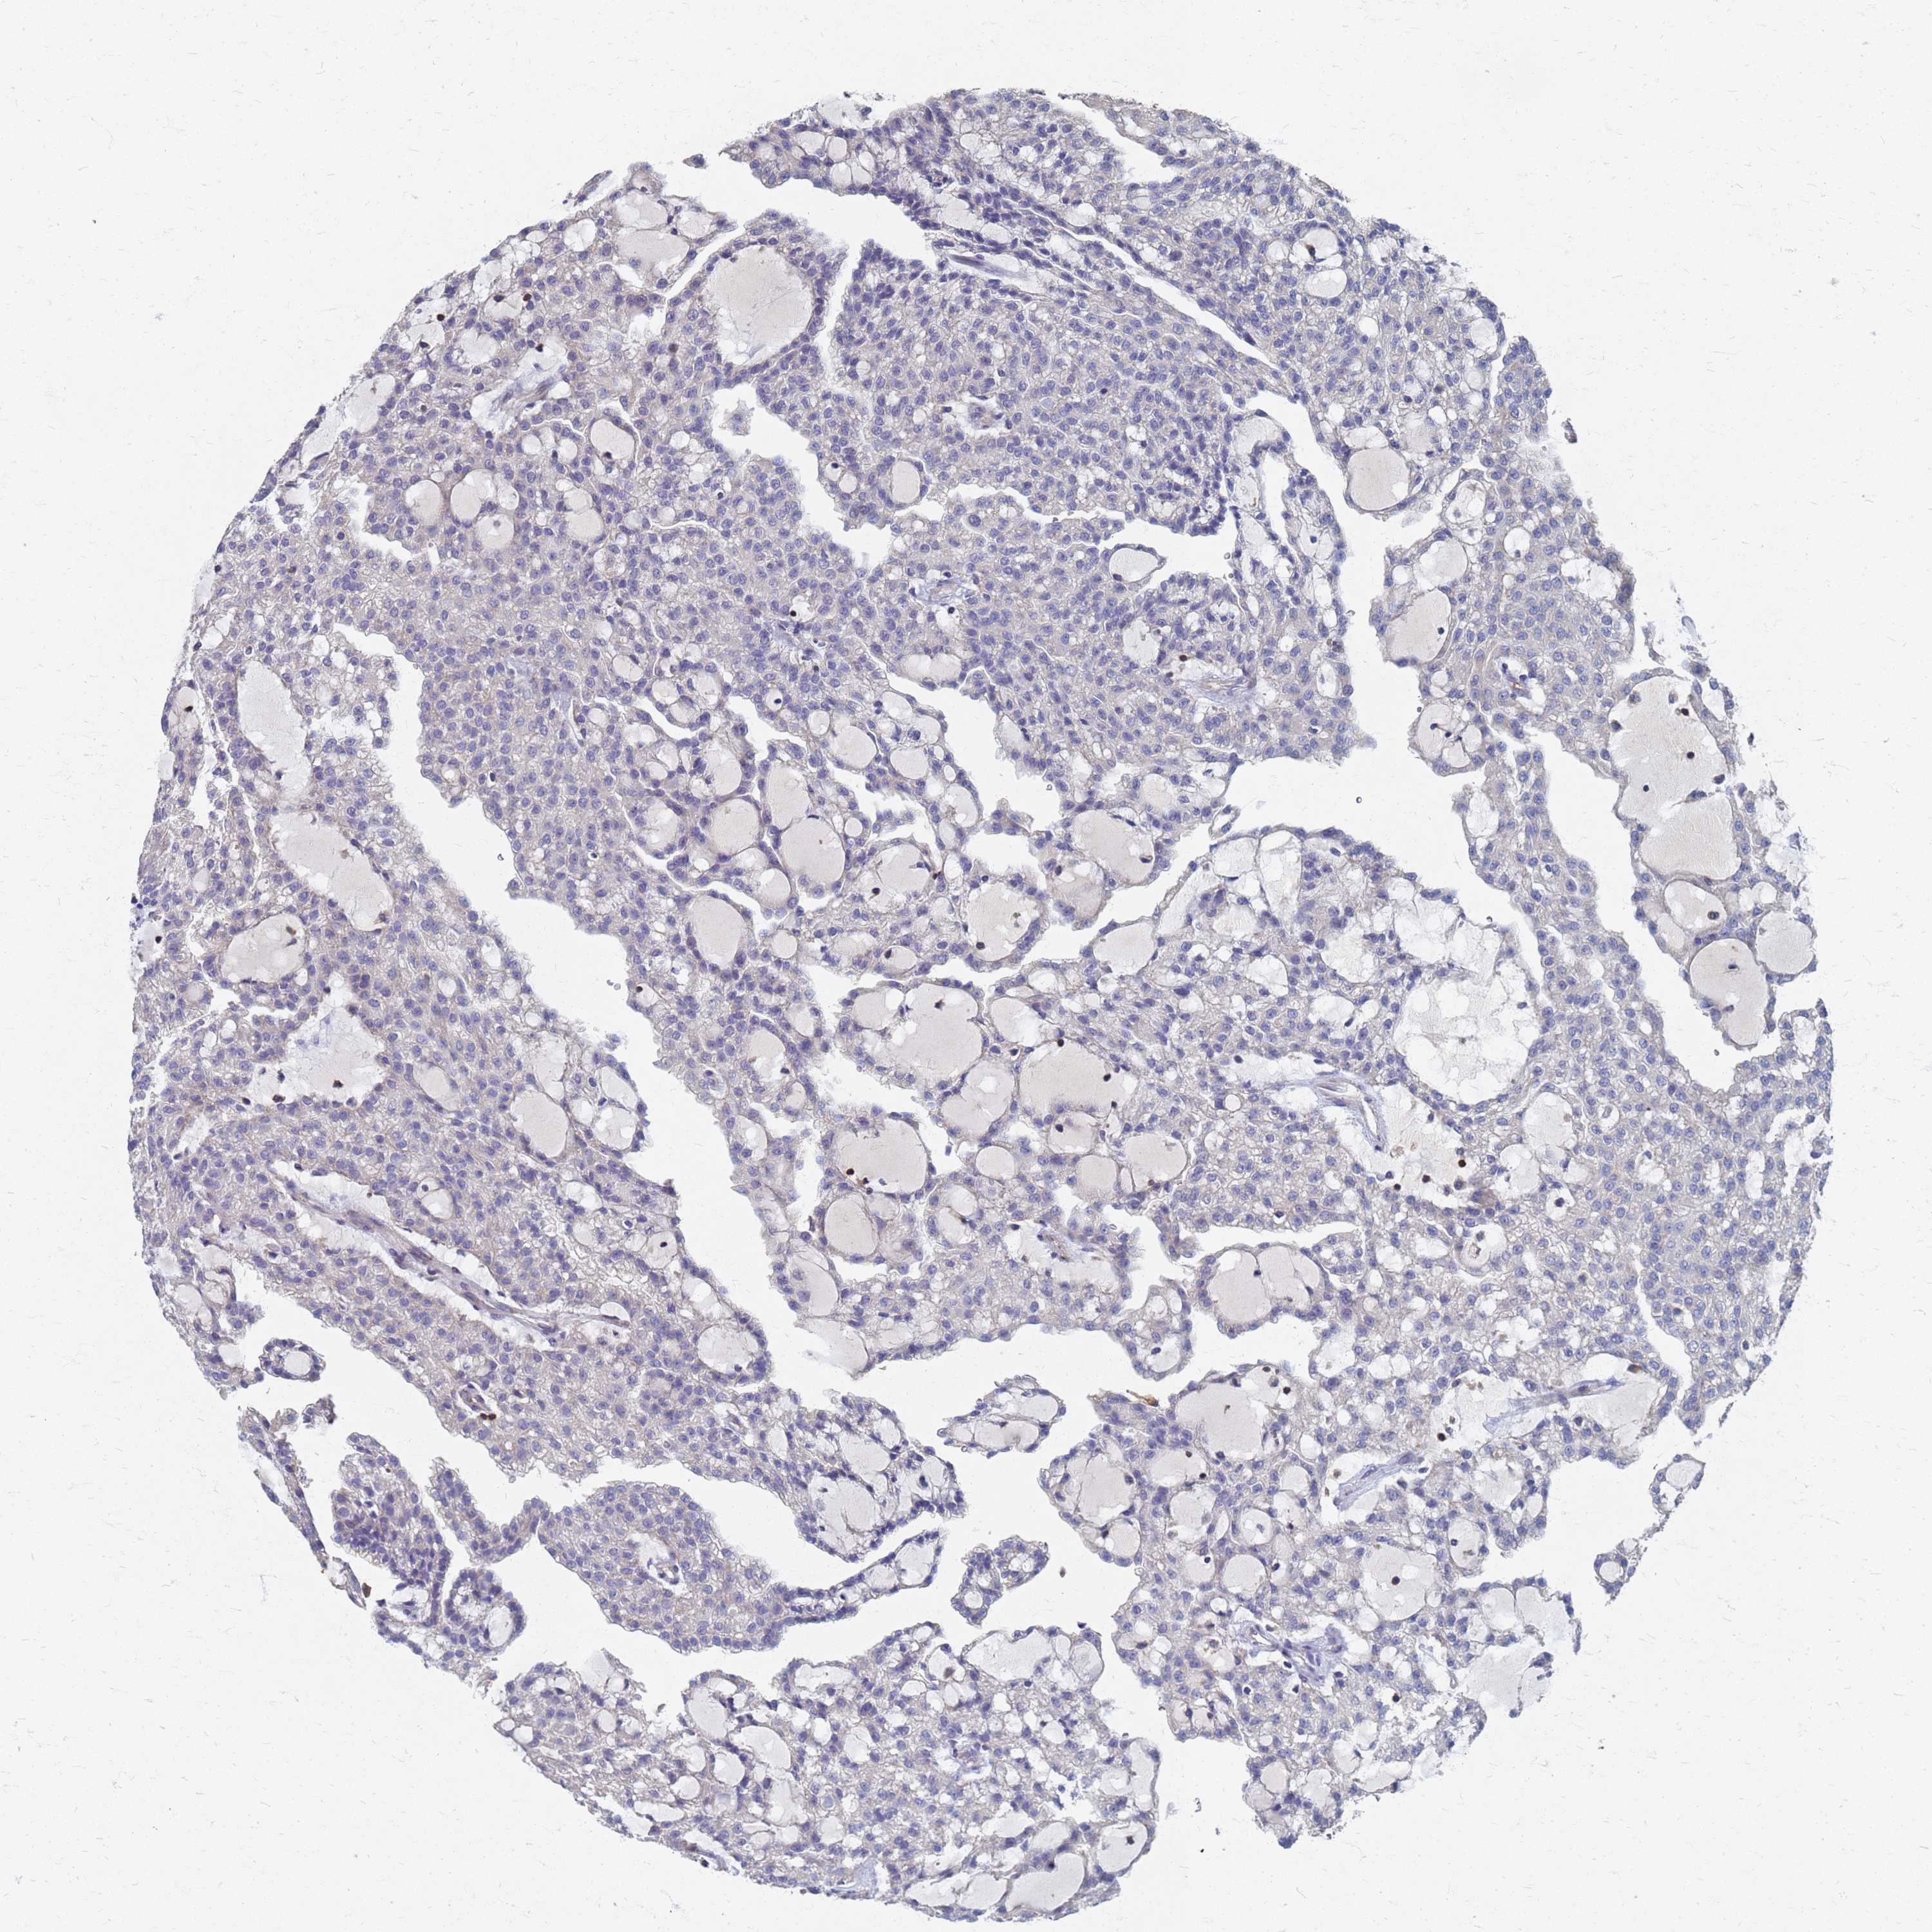

KIDNEY RENAL PAPILLARY CELL CARCINOMA (TCGA) - Interactive survival scatter ploti

The Survival Scatter plot shows the clinical status (i.e. dead or alive) for all individuals in the patient cohort, based on the same data that underlies the corresponding Kaplan-Meier plots. Patients that are alive at last time for follow-up are shown in blue and patients who have died during the study are shown in red.

The x-axis shows the expression levels (FPKM) of the investigated gene in the tumor tissue at the time of diagnosis. The y-axis shows the follow-up time after diagnosis (years). Both axes are complimented with kernel density curves demonstrating the data density over the axes. The top density plot shows the expression levels (FPKM) distribution among dead (red) and alive patients (blue). The right density plot shows the data density of the survived years of dead patients with high and low expression levels respectively, stratified using the cutoff indicated by the vertical dashed line through the Survival Scatter plot. This cutoff is automatically defined based on the FPKM cutoff that minimizes the p-score. The cutoff can be changed by dragging the vertical line or by entering a cutoff value in the square labeled "Current cut-off".

Under the Survival Scatter plot the p-score landscape (black curve; left axis) is shown together with dead median separation (red curve; right axis). Dead median separation is the difference in median mRNA expression between patients who have died with high and low expression, respectively. It is calculated as follows: median FPKM expression of dead patients with high expression - median FPKM expression of dead patients with low expression. This is intended to aid the user in visually exploring custom cutoffs and the associated p-scores and dead median separation.

Individual patient data is displayed and can be filtered by clicking on one or more of the category buttons on the top of the page. Categories describing expression level and patient information include: high, low, alive, dead, female, male and tumor stages. The scale of the x-axis can be toggled between linear and log-scale by clicking on the "x log" button. Mouse-over function shows TCGA ID, patient information and mRNA expression (FPKM) for each patient.

& Survival analysisi

Kaplan-Meier plots summarize results from analysis of correlation between mRNA expression level and patient survival. Patients were divided based on level of expression into one of the two groups "low" (under cut off) or "high" (over cut off). X-axis shows time for survival (years) and y-axis shows the probability of survival, where 1.0 corresponds to 100 percent.

KRCC1 is not prognostic in Kidney Renal Papillary Cell Carcinoma (TCGA)